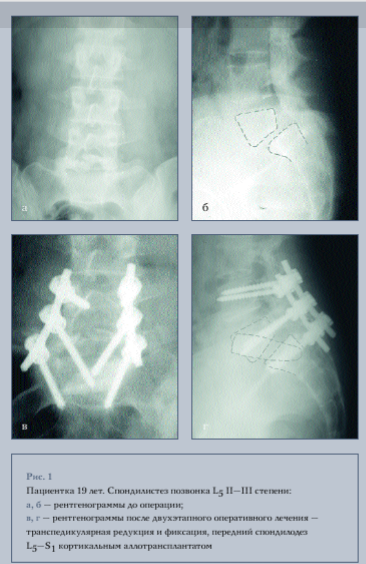

В зависимости от уровня фиксации мы разделили больных на 4 группы: больным I группы произведена фиксация двух сегментов, винты вводились в L4, L5 и S1 позвонки (рис. 1); в остальных группах производилась фиксация трех сегментов, при этом во II группе винты вводились в L3, L4, L5 и S1 позвонки, в III - в L3, L5 и S1 позвонки и в IV группе в L3, L4 и S1 позвонки (рис. 2).

Всем пациентам осуществляли задний и заднебоковой спондилодез аутотрансплантатами из резецированных остистых отростков и из гребня подвздошной кости. Межтеловой спондилодез L5-S1 выполняли 28 пациентам. Двум пациентам после проведенной редукции и фиксации пояснично-крестцового отдела транспедикулярной конструкцией из заднего доступа выполняли корпородез кейджами Interfix, заполненными костной аутокрошкой.

Межтеловой спондилодез из переднего внебрюшинного доступа выполняли 22 пациентам, из них 15 - кортикальным аллотрансплантатом, 2 - аутотрансплантатом из гребня подвздошной кости и 5 - комбинацией алло- и аутотрансплантатов. Сроки выполнения второго этапа были различными. Одному пациенту он был выполнен сразу после дорсального вправления и фиксации, остальным - второй этап проводили в различные сроки после первой операции: до одного месяца - 10 пациентам, до трех месяцев - 5, свыше трех месяцев - 5 пациентам.